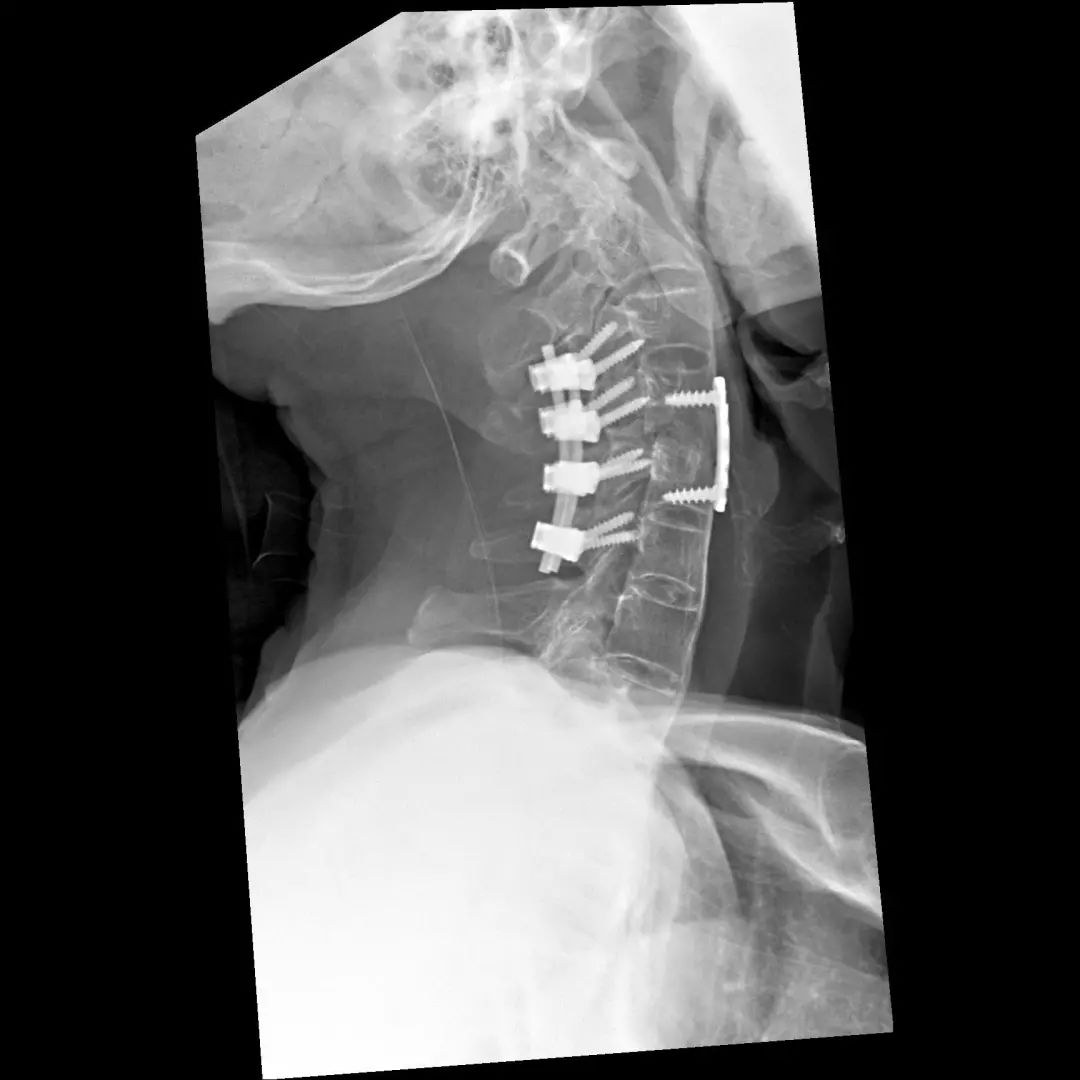

经过全程监护和系统治疗,患者术后恢复良好,骨折解剖复位,复查X线及CT显示固定位置佳,术后3天下地行走,术后4天即出院回家休养。

该手术为我市首例完成C1、2椎弓根钉棒系统固定手术,填补了枣庄在上颈椎外伤手术史上的空白,展现了枣庄市立医院脊柱外科不怕困难、勇于突破、积极向上的精神面貌,也是王存平主任技术高超、胆大心细的具体体现。

“宝剑锋从磨砺出,梅花香自苦寒来。”目前,枣庄市立医院脊柱外科在上颈椎损伤治疗方面取得长足发展,对于枢椎齿状突骨折,已能独立开展前路空心螺钉固定、后路Margerl手术、后路椎弓根钉棒固定术,在上颈椎外伤治疗方面处于省内领先。